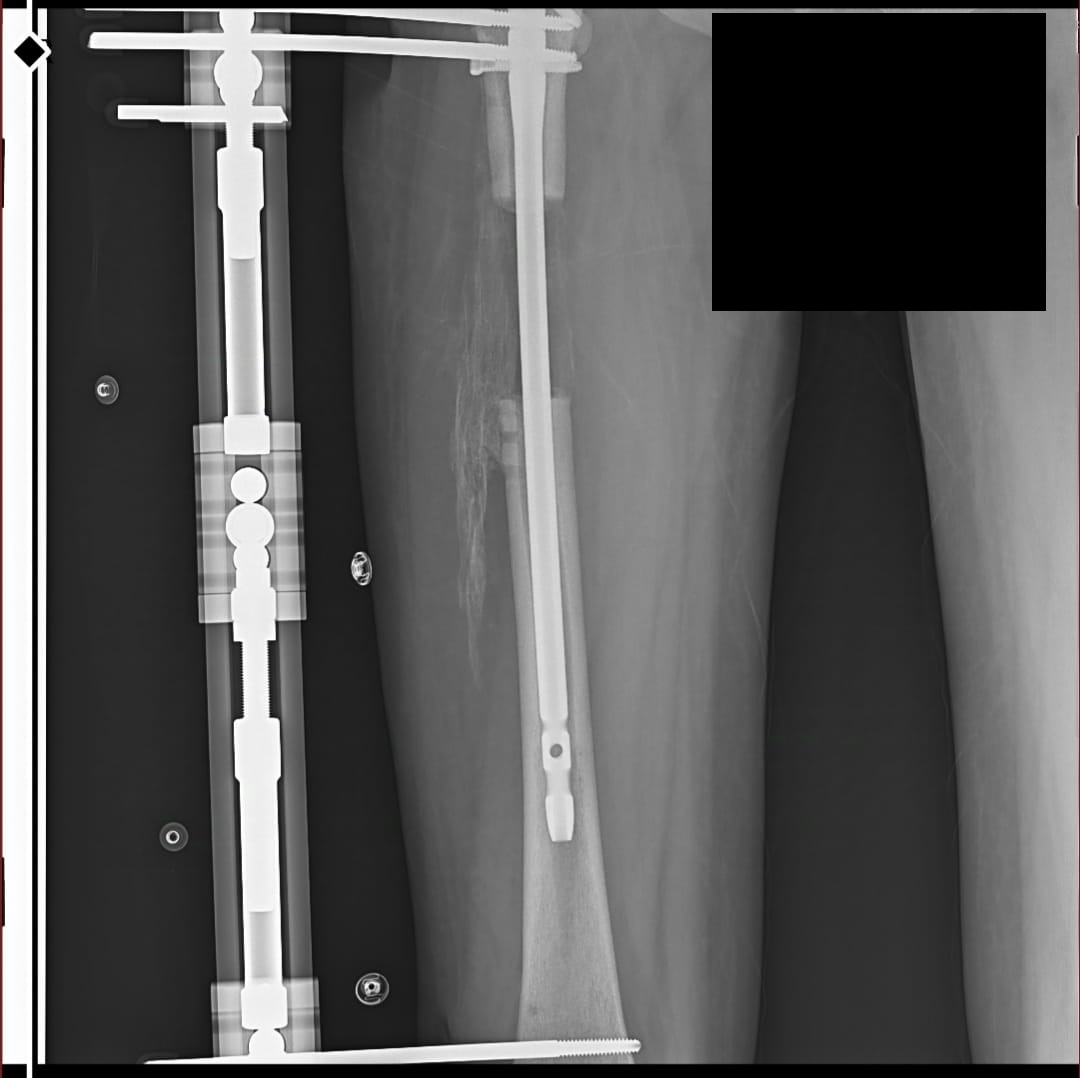

these are my xrays chronologically00 -

these are just before removing external fixatorAttachments: